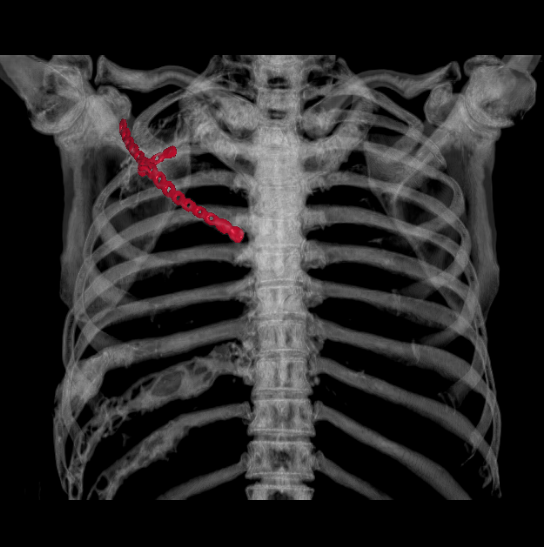

近日,重慶醫(yī)科大學(xué)附屬璧山醫(yī)院(重慶市璧山區(qū)人民醫(yī)院)胸心血管外科為患者實(shí)施全院首例胸壁腫物切除+胸壁重建術(shù),成功為患者去除病灶,目前患者已康復(fù)出院。

榮騰浩副主任醫(yī)師、楊富瑜主治醫(yī)師經(jīng)過全面檢查,研究病例后認(rèn)為:巨大腫物切除后,胸壁“軟化”為常見并發(fā)癥,進(jìn)而導(dǎo)致反常呼吸,影響心肺功能,而患者為體力勞動(dòng)者并且是家庭經(jīng)濟(jì)支柱,“重建”胸廓可使患者恢復(fù)勞動(dòng)能力。胸心血管外科團(tuán)隊(duì)制定完善手術(shù)計(jì)劃后,決定手術(shù)切除后予以Matrix -RIB板重建,手術(shù)過程順利,術(shù)后無并發(fā)癥,目前患者已康復(fù)出院。